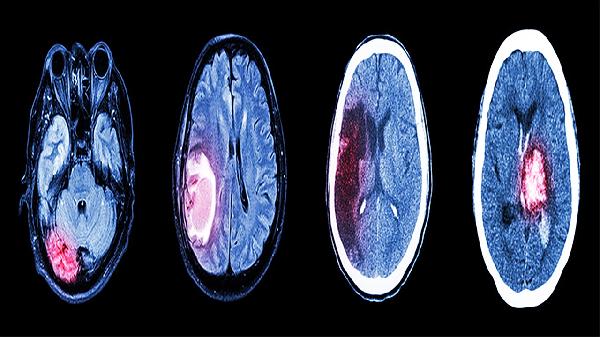

重度颅脑损伤的诊断标准是什么

重度颅脑损伤的诊断标准主要包括意识障碍程度、影像学检查结果、生命体征异常以及神经系统症状等。诊断时需结合格拉斯哥昏迷评分、头颅CT或MRI检查、瞳孔反应及肢体活动情况综合评估。1.意识障碍程度 格拉